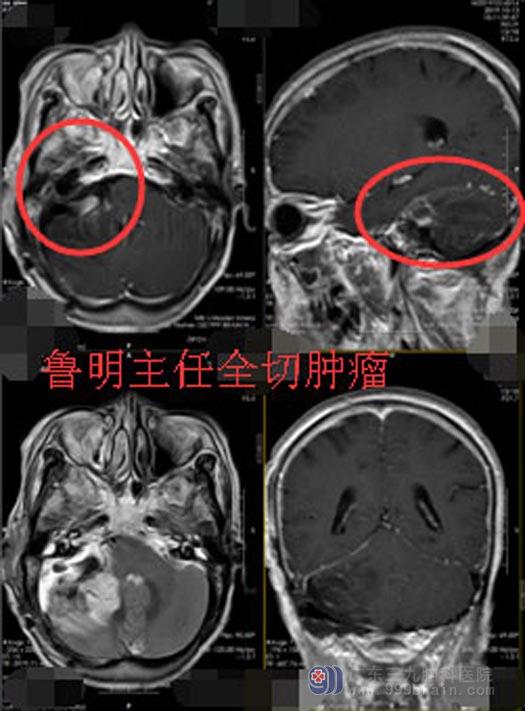

术后,徐阿姨神志清楚,回答正确,可遵嘱活动,饮水无呛咳,未出现面瘫症状,自诉右耳听力较前好转。徐阿姨一家对手术效果非常满意。

▲手术后